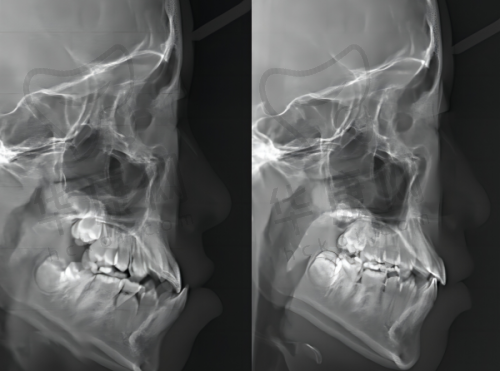

江门万国口腔引进了全数字化的口腔设备和技术,如ITero矫正口扫仪器、CS3600口内扫描器等。这些高端设备提高了诊疗的精细度和患者的就诊体验。以ITero矫正口扫仪器为例,它可以快速、正确地获取患者口腔的三维数据,医生能够更直观地了解患者牙齿的情况,从而制定出更精细的矫正方案。而CS3600口内扫描器则能为牙齿修复等项目提供详细的口腔内部图像,大大提高了诊疗的效率和正确性。这些设备的引进,使得江门万国口腔医院在口腔诊疗方面更加专精和效率高。